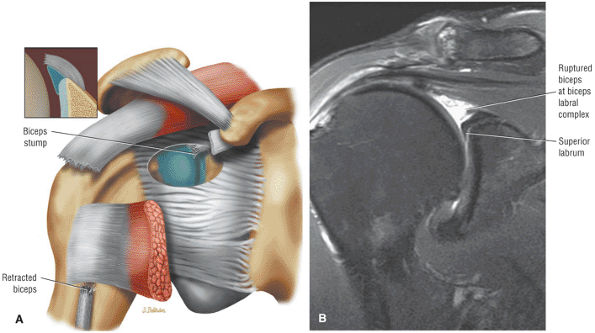

stripped from its lesser tuberosity attachment. However, because of an intact connection with the transverse humeral ligament, which connects the subscapularis tendon to the greater tuberosity, the tendon fibers appear to course in continuity without retraction. Proximal biceps tendon and subscapularis tendon pathology commonly coexist, since the pathogenesis of tendinosis and tears of both tendons are interrelated.